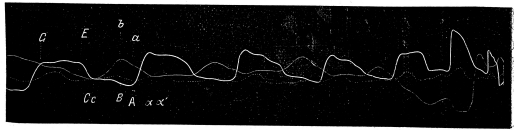

Послѣ изученія флебограммъ на животныхъ я перешелъ къ снятію колебаній вены у людей. Приведу изъ этихъ наблюденій 4 случая, ясно демонстрирующія различныя формы веннаго пульса.

Въ 1-омъ случаѣ у больной, страдавшей, кромѣ недостаточности митральнаго клапана, стенозомъ лѣваго венознаго кольца, (пресистолическій и систолическій шумы ad арісеш) слышался систолическій шумъ и на нижнемъ концѣ грудины и былъ рѣзко выраженный пульсъ венъ; размѣры сердца перкуторно были значительно увеличены, при этомъ имѣлось значительное нарушеніе компенсаціи сердца.

Флебограмма этого случая, изображенная на фиг. 16 а и b отличается рѣзкими особенностями отъ предыдущихъ тѣмъ, что ея предсердіальная волна (bс) очень мала, едва замѣтна; желудочковая волна крайне незначительна во время періода напряженія систолы желудочка (се) и подъемъ начинается лишь съ наступленіемъ 2-го періода систолы желудочка и продолжается не только во время систолы, но и начала его діастолы. На вершинѣ этой волны (eg) имѣется цѣлый рядъ мелкихъ волнъ, какъ на plateau systolique кардіограммы.

Уменьшеніе предсердіальной волны объясняется слабостью сокращенія предсердія, которое не можетъ послать сильную волну въ вену и тѣмъ, что застоя въ венѣ при систолѣ его образоваться не можетъ, такъ какъ венный затворъ не функціонируетъ и кровь свободно стекаетъ въ предсердіе, какъ въ легко растяжимый мѣшокъ.

Слабостью же мускулатуры желудочка должно объяснить отсутствіе подъема въ венѣ во время 1-го періода систолы желудочка.

Въ это время кровь оттекаетъ обратно подъ столь малымъ давленіемъ, что оно не можетъ произвести набуханія вены, и только при болѣе энергичномъ сокращеніи желудочка во время періода изгнанія образуется болѣе сильный оттокъ крови, обусловливающій повышеніе давленія въ венѣ и подъемъ еg на флебограммѣ въ это время. Продолженіе подъема желудочковой волны и во время діастолы желудочка должно объяснить передачей пульсацій сосѣдней артеріи на вену.

Фиг. 16a

Фиг. 16b

Черезъ нѣсколько мѣсяцевъ по снятіи кривой эта больная скончалась. При вскрытіи сердце оказалось громаднымъ (corbovinum), митральный клапанъ сморщеннымъ, лѣвое венозное отверстіе едва пропускающимъ мизинецъ; правое венозное кольцо было весьма расширено, точно также найдены расширенными и отверстія венъ, особенно впадающихъ въ правое предсердіе, полости сердца значительно растянуты, стѣнки предсердій и желудочковъ истончены; при микроскопическомъ изслѣдованіи констатированы явленія міокардита.

Флебограмма, нарисованная на фиг. 17-й а и b, получена отъ второй больной, имѣвшей недостаточность митральнаго клапана и суженіе лѣваго венознаго отверстія сердца и ясно выраженныя пульсаціи яремной вены. Въ данномъ случаѣ, при перкусіи, правая граница сердца шла на 1/2 сант. вправо за правымъ краемъ грудной кости, лѣвая граница проходила сант. на 2 кнаружи отъ 1. mamillaris sin. Сердечный толчекъ тоже былъ смѣщенъ влѣво за 1. mamillaris сант. на 2, былъ разлитой и ощупывался всего яснѣе въ 5-мъ межреберномъ промежуткѣ. На флебограммѣ этой больной отразилось вліяніе дыхательныхъ движеній, вслѣдствіе чего волны ея сдѣлались не вполнѣ равномѣрными; на кардіограммѣ удлинилась большая пауза, что зависало отъ возбужденія блуждающихъ нервовъ при временныхъ остановкахъ дыханія больной.

Въ отличіе отъ предыдущаго случая, въ флебограммѣ 17-й имѣется ясная предсердіальная волна (ас) съ болѣе раннимъ началомъ вслѣдствіе передачи пульсацій сосѣдней артеріи на вену; подъемъ, весьма незначительный, желудочковой волны (сеg) отмѣчается во время 1-го періода систолы желудочка. Съ наступленіемъ 2-го періода флебограмма круто поднимается вверхъ и держится почти на одной высотѣ до окончанія сокращенія желудочка, образуя при концѣ спуска клапанную волну g.

Это все заставляетъ признать, что въ данномъ случаѣ при подобномъ же заболѣваніи, какъ и въ предыдущемъ наблюденіи слабость мышцы предсердія была меньше выражена, желудочка же одинаково сильно.